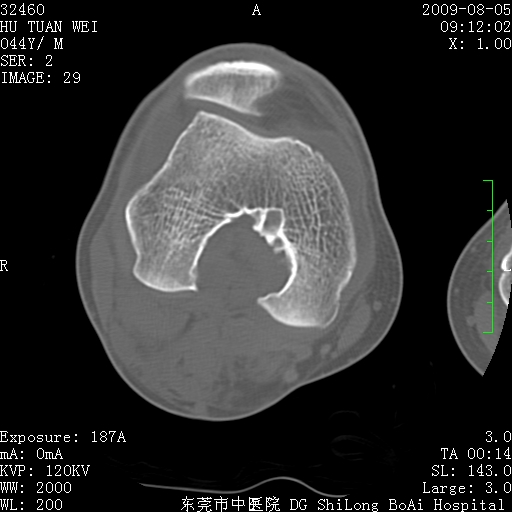

标题: CT21940:膝关节(有病理)

中年男性,膝韧带损伤术前检查!其他病史不清粗,不是我接手病人、且出院了!

1、股骨下段囊状膨胀性病变,边缘硬化明显,内多个残留骨棘呈多房型改变,囊腔密度较高无钙化,膝关节滑膜囊增厚,密度增高,关节腔少量积液。考虑:邻关节囊肿、退变性囊肿(软骨下囊肿)、着色性绒毛结节性滑膜炎、abc、骨巨、良性纤维组织细胞瘤等鉴。虽然年龄偏大,部位于骨端,但有外伤史,本人还是倾向于动脉瘤样骨囊肿(abc)可能性大。邻关节囊肿及软骨下囊肿次之考虑。

2、胫骨髁间棘撕脱骨折,交叉韧带损伤可能;

3、关节退行性改变。

病理结果:色素沉着绒毛结节性滑膜炎

感谢反馈病理结果!本病为慢性关节病变。以关节滑膜高度增生、绒毛结节形成伴含铁血黄素趁着为特点。病因:有炎症、肿瘤、外伤关节出血、代谢障碍、变态反应及感染等学说。增强扫描呈关节腔内单个或多个强化的软组织结节影或滑膜不规则增厚伴关节积液为本病的特征性表现。